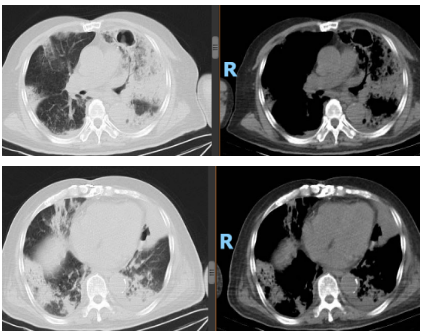

2025-10-31(入院27天后)复查

1. 超敏C反应蛋白:45.30mg/L↑。

2. 血常规:白细胞计数 7.28*109/L,中性粒细胞计数 5.27*109/L,中性粒细胞百分比 72.30%↑,淋巴细胞百分比 13.20%↓,淋巴细胞绝对值 0.96*109/L↓,血红蛋白 88g/L↓,血小板计数162*109/L。

3. BNP:376.60pg/mL↑。

4. 肝肾功能:基本正常,白蛋白 27g/L↓。

5. 复查血气分析(无创呼吸机辅助通气,S/T模式, IPAP 14cmH2O,EPAP 6cmH2O,氧浓度28%):PH 7.490,PCO2 40mmHg,PO2 61.2mmHg↓,SO2 93%,cK+ 3.36, cNa+ 141mmol/L,cCL- 104mmol/L,cLac 1.39mmol/L,cGlu 5.18mmol/L ,PaO2/FiO2 218.57mmHg↓↓↓。